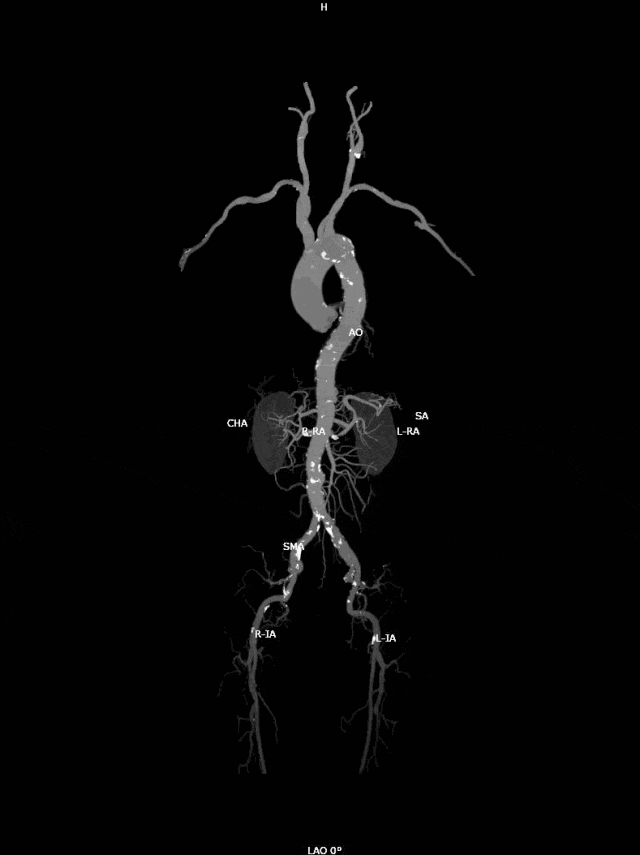

近日,吴爷爷因为慢性支气管炎急性发作,到奉城医院呼吸科住院治疗,住院期间进行CT检查,CT报告显示:主动脉弓部动脉瘤可能?

夏向红医生收到报告后,马上联系血管外科宋菊民主任进行会诊,完善肺动脉CTA(CT血管造影)。

复查报告显示主动脉弓动脉瘤伴血栓形成可能